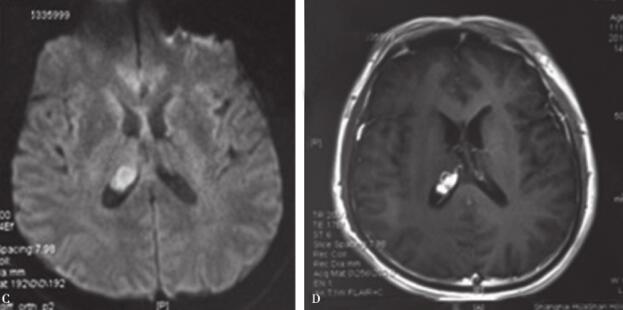

患者,男性,44岁。警察职业。今年3月份以来出现双下肢乏力,7月份出现反复头痛,8月中旬出现伴意识模糊。头颅CT及MRI提示颅内多发病变,右侧侧脑室结节样病变(图1,图2)。按“感染性肉芽肿”予抗感染治疗,患者症状有一定改善,仍有反应迟钝。转入我科治疗。

图2 颅内多发病变(FLAIR像)

A.双侧钩回-海马-杏仁核病变;B.双侧海马,小脑病变;C、D.小脑病变